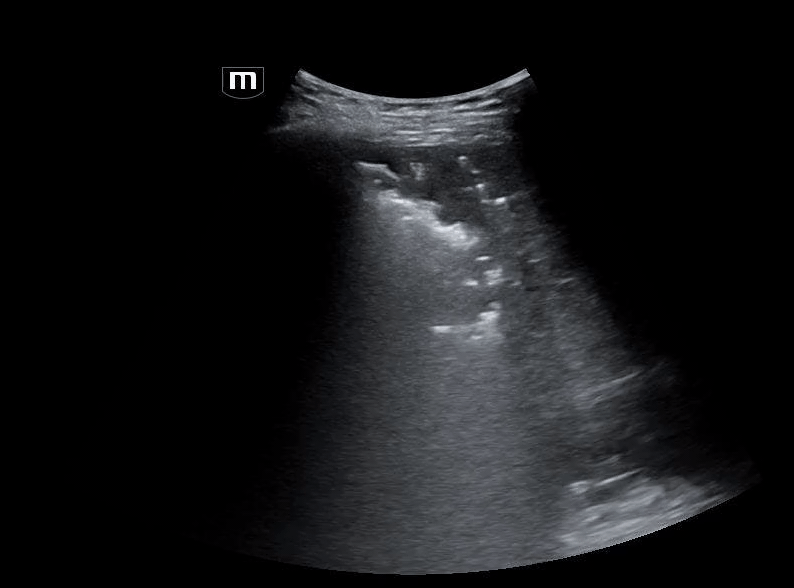

Using the linear probe for better visualization of superficial structure, let’s take a look at what we saw on the left lower leg:

What do we see?? Air and “dirty shadowing” in the soft tissue concerning for necrotizing fasciitis in this clinical context.

We can identify necrotizing fasciitis on US by using the acronym “STAFF”

• S – Subcutaneous thickening: diffuse thickening and distortment of soft tissue layers seen

• T – Thickened fascia:  chunky fascia not a thin bright white line

• A – Air: posterior dirty acoustic shadowing, corresponding to gas in the soft tissue

• F – Fascial fluid: Anechoic fluid collections (<2mm)